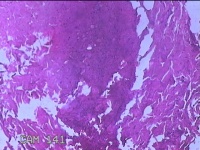

性别

男

年龄

27岁

临床诊断

皮下结节

一般病史

发现下颌部结节1·个月余,伴局部隐痛不适。

标本名称

下颌部结节

大体所见

灰白暗红色结节0.8x0.5x0.2cm一个,表面糜烂。